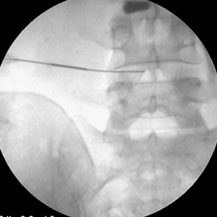

Ozone neucleolysis or ozone discectomy is a non-operative intervention for slipped disc / disc prolapse & discogenic pain. Ozone discectomy is a day care procedure and general anaesthesia is not required. Total cost of the procedure is much less and is very safe compared to other procedures. It has been implicated as one of the important cause of low back pain radiating to limbs. Apart from conservative therapy all other forms of treatment aim at decompressing the nerve roots. These can be done by taking the disc out by surgery or by decompressing the foremen and disc by different interventions. The various treatment options have confused clinicians due to significant failure rate associated with different kinds of surgeries as well as with different interventions.

Epidural steroid injection, transformational epidural decompressions has a high success rate (up to 85%) but chances of recurrences are there specially if these interventions are done at later stage. Chemonucleolysis using chymopa pain has also high success rate (80%) with low recurrences but not popular owing to the chances of anaphylaxis following intradiscal chymopa pain injection. Injection of ozone for discogenic radiculopathy (low back pain with radiation to legs) has developed as an alternative to chemonucleolysis and disc surgery owing to its high success rate, less invasiveness, fewer chances of recurrences and remarkably fewer side effects.

The action of ozone is due to the active oxygen atom liberated from breaking down of ozone molecule. When ozone is injected into the disc the active oxygen atom called the singlet oxygen or the free radicle attaches with the proteo-glycan bridges in the jelly-like material or nucleus pulposus. They are broken down and they no longer capable of holding water. As a result disc shrinks and mummified and there is decompression of nerve roots. It is almost equivalent to surgical discectomy and so the procedure is called ozone discectomy or ozonucleolysis. Besides, it has an anti-inflammatory action due to inhibitions of formation of inflammation producing substances and tissue oxygenation is increased due to increased 2,3 diphosphoglycerate level in the red blood cells. All these leads to decompression of nerve roots, decreased inflammation of nerve roots, increased oxygenation to the diseased tissue for repair work.

Ozone nucleolysis or ozone discectomy has a success rate of about 80%. On the other hand surgical discectomy has much higher side effects compared to remarkably few side effects of ozone discectomy. Ozone discectomy is usually a day care procedure and general anaesthesia is not usually required. Total cost of the procedure is much less than that of surgical discectomy. All these facts have made this procedure very popular at European countries. It is also gaining popularity in our country due to low cost, less hospital stay, no post-operative discomfort and morbidity and very few side effects.